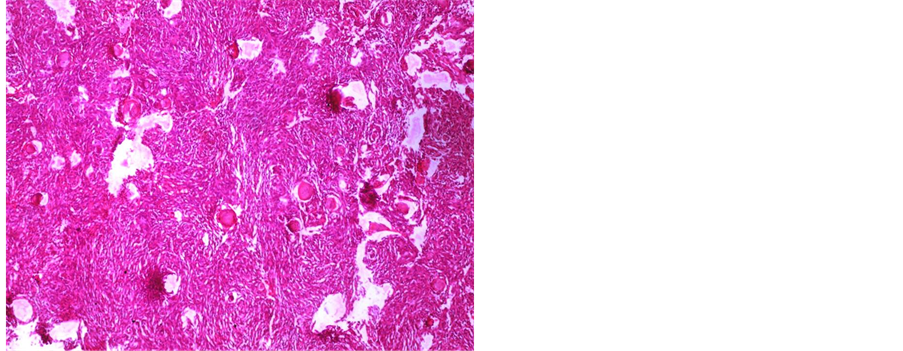

A 61-year-old female patient was with history of spinal trauma in 26 year ago. Patient fall down from height and had a traumatic L1 fracture. Patient was managed conservatively at that time as she refused surgical intervention and had no neurological deficit. Patient experienced frequent attacks of low back pain and rarely sciatic pain that was treated with analgesia. 6 months ago, the patient had a progressive heaviness in both lower limbs with urinary incontinence and visited the outpatient clinic. On examination, the patient was paraparetic with motor power grade II or III below L1. Patient had hypotheisa below L1 with diminished knee and ankle reflexes. MRI lumbar and dorsal spine showed the post-traumatic L1 fracture with a new large intra-dural mass most probably meningioma or schwnoma as shown in Figure 1. Patient operated with posterior lumbar approach including posterior L1 and D12 laminectomy. Total standard microscopic excision of the intra-dural soft tissue mass with moderate vascularity was performed successfully. A posterior D11, D12 and L2 trans-pedicular screw fusion was performed at the end of the procedure. Histopathological examination revealed multiple nodules of proliferated meningothelial cells separated by delicate fibrous tissue, with thick walled blood vessels and calcified psammoma bodies together with oval to rounded cells with oval nuclei, occasional nuclear clearing and infrequent mitosis arranges in whorly pattern with rounded calcified psamma bodies. A meningeothelial and psamomatous meningioma was reported as shown in Figure 2. The patient has smooth postoperative course with improvement of her neurological deficit with physiotherapy. 4 months after surgery, the patient was able to ambulate without assistance. On her last follow up after one year of surgery; the patient has no neurological deficit and can ambulate without assistance

Figure 2. (a) Photomicrograph showing multiple nodules of proliferated meningothelial cells separated by delicate fi- brous tissue, with thick walled blood vessels and calcified psammoma bodies, H & E × 40 (b) and (c) Photomicr- graph of meningioma showing oval to rounded cells with oval nuclei, occasional nuclear clearing and infrequent mi- tosis arranges in whorly pattern with rounded calcified psammoma bodies, H & E × 400.